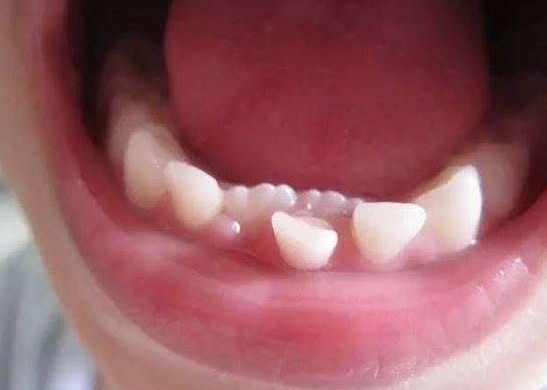

黃女士的兒子「樂樂」今年8歲,他同學從6歲開始就陸續換牙了,他卻一直沒動靜,直到8歲後他才出現換牙的情形。由於舊的乳牙沒及時脫落,而下排牙齒中間長出的兩顆新牙,被擠在一起了,中間還有半顆牙的空隙,看上去就像長了雙排的異形牙。醫生看過後,說這是兒童常見的狀況,但是責任是在家長身上。

也建議換牙期的孩子應該多吃一些粗糧和未經細緻加工的食物,食品對乳牙的刺激能促使乳牙正常脫落,應該鼓勵孩子多吃些硬質粗纖維食物比如豆類、堅果類和粗糧。

所以偏愛甜食飲料,過於精緻的點心,長期吃不太需要咀嚼的食物都是造成「雙排牙」的主因。為了要預防,牙醫呼籲爸媽還是要仔細觀察,如果一有出現「雙排牙」的狀況一定要儘快找牙醫處理!不然之後長出來的牙可能會偏位。